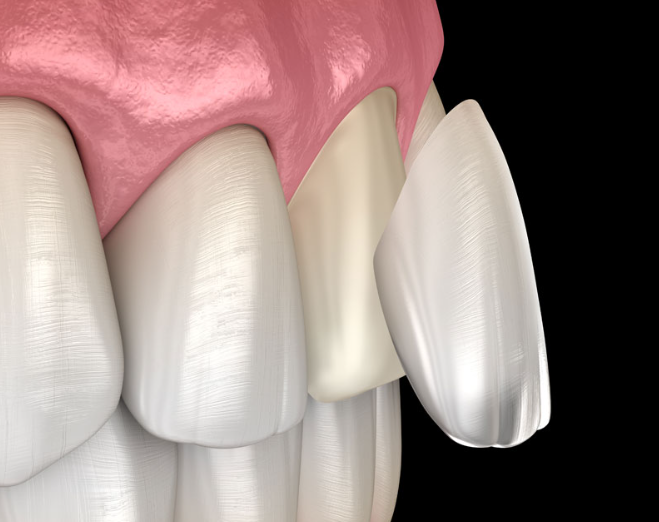

요즘 많이 하시는 라미네이트 치료 역시

단순히 붙이는 시술로 보일 수 있지만,

그 안에는 섬세한 접착 기술이 바탕이 되어야만 좋은 결과를 기대할 수 있습니다.

우리가 욕실에 사용하는 타일을 생각해볼까요?

타일 하나하나는 살짝의 충격으로도 깨질 수 있습니다.

하지만 적절히 사용하는 시멘트를 이용하여 벽에 잘 붙여진 타일은

보다 강한 충격에도 쉽게 깨지지 않습니다.

적절한 재료와 기술로 잘 접착되었기 때문이죠.